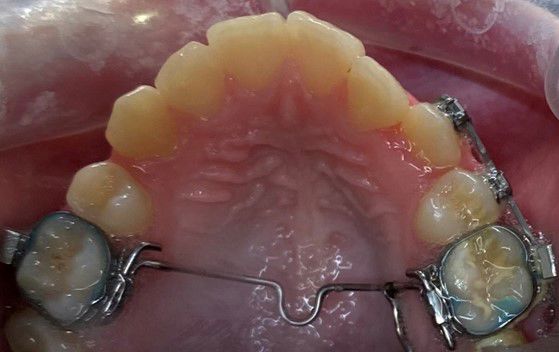

Bruges til at udvide tandbuen i overkæben, f.eks. ved krydsbid.

Den er fastgjort til 6-års tænderne med 2 bånd.

Bruges til at udvide ganen.

Den limes fast på tænderne. Der skal skrues i midten af bøjlen, I får en grundig instruktion på tandreguleringsklinikken.

Der kan opstå lidt spænding ved tænderne, næsen og evt. mellem øjnene.

Ofte kommer der et mellemrum ved fortænderne i en periode.